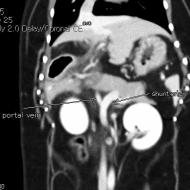

• 질환 PSS, 에디슨 그외 복합 호르몬질환

PSS와 에디슨이 동시 진단

희귀질환인 PSS와 에디슨이 두 가지나 공존해 있었고, 간과 부신에도 문제가 있었습니다.

이후에 갑상선, 간, 부신이

서로 밀접하게 연결되어 있다는 사실을 알게 됩니다.

PSS는 선천적 질환이며, 대부분 수술을 하지 않으면 어린 나이에 폐사하게 됩니다.